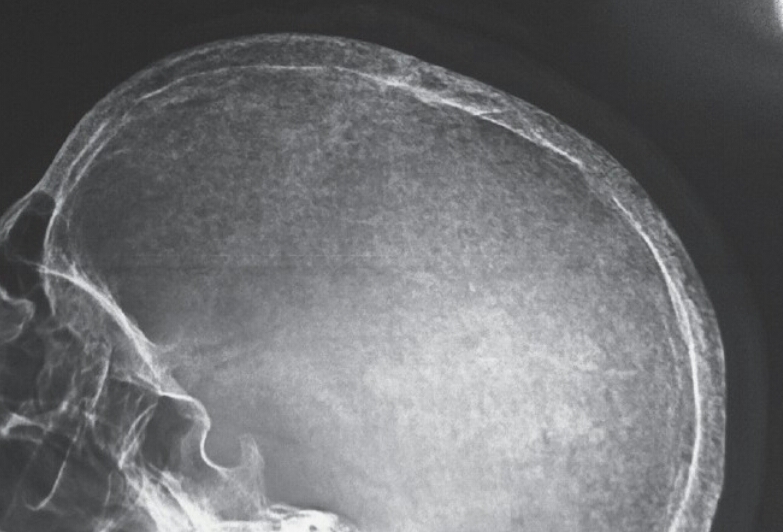

What is the radiographic feature? What disease is this associated with?

salt and pepper skull

HPT